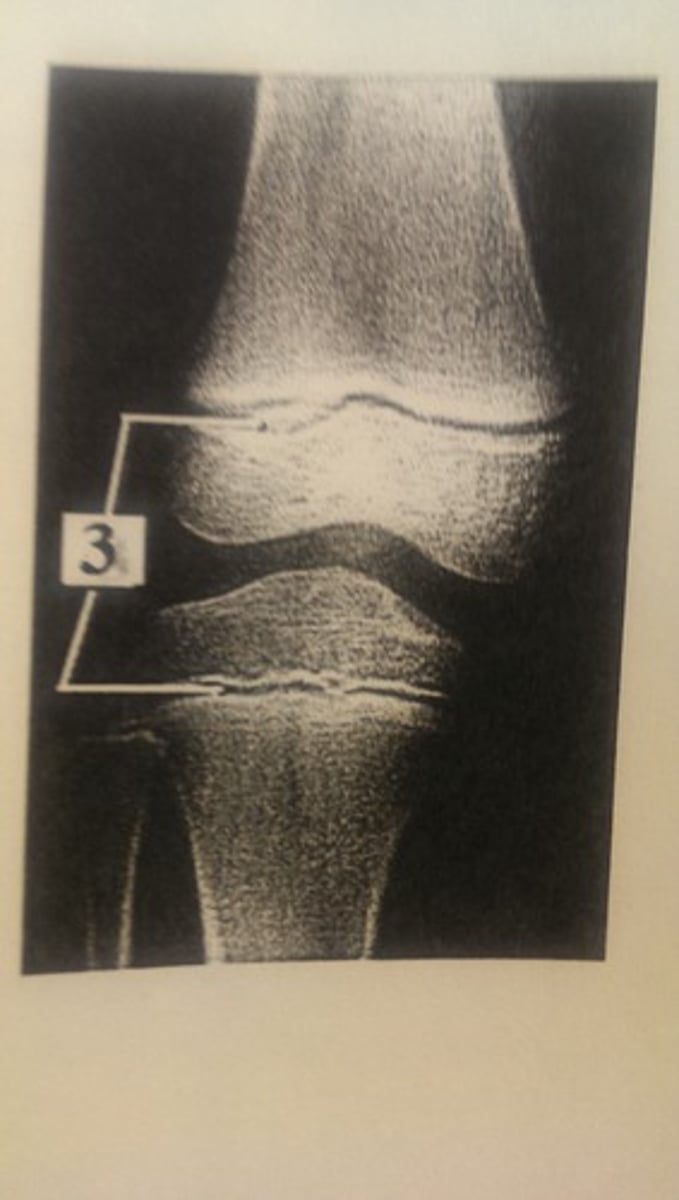

Epiphyseal plate

Proximal epiphysis

Articular cartilage

Cancellous (spongy) bone

epiphyseal line